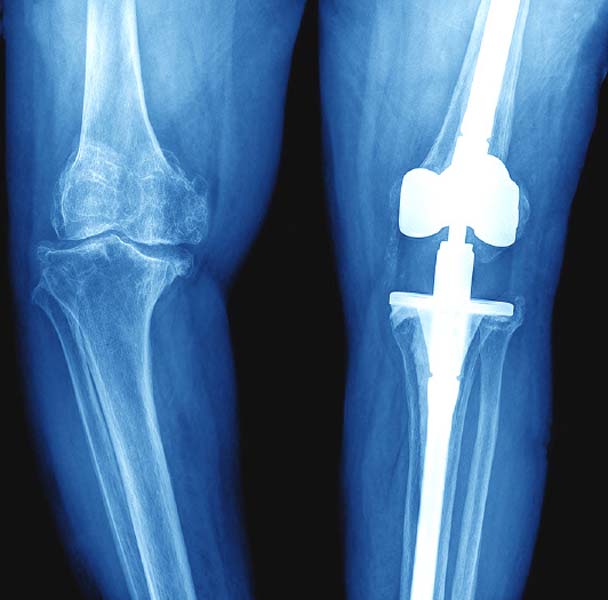

ผ่าตัดแก้ไขข้อเข่าเทียม คืนคุณภาพให้ข้อเข่าอย่างมีประสิทธิภาพ

ข้อเข่าใครคิดว่าไม่สำคัญหากเกิดปัญหาหลังผ่าตัดเปลี่ยนข้อเข่าเทียม ไม่ว่าจากข้อเทียมหลวม ได้รับอุบัติเหตุ หรือเกิดการติดเชื้อของข้อเข่าเทียมที่เคยได้รับการผ่าตัดมาก่อนหน้านี้ ผู้ป่วยจะมีอาการปวด บวม เกิดปัญหาในการใช้ชีวิตประจำวัน ทั้งนี้ การผ่าตัดแก้ไขข้อเข่าเทียมถือเป็นทางเลือกหนึ่งที่ช่วยให้ผู้ป่วยสามารถกลับมาใช้ชีวิตอย่างมีคุณภาพได้อีกครั้ง

นายแพทย์วัลลภ สำราญเวทย์ ผู้อำนวยการศูนย์ข้อสะโพกและข้อเข่ากรุงเทพ โรงพยาบาลกรุงเทพ ให้ข้อมูลว่า โดยทั่วไปแล้วข้อเข่าเทียมสามารถใช้งานได้นาน โดยไม่ต้องผ่าตัดซ้ำ อย่างไรก็ตาม บางครั้งข้อเข่าเทียมอาจจำเป็นต้องได้รับการแก้ไข อันเนื่องมาจากสาเหตุต่างๆ โดยจะมีอาการแสดงคือ อาการปวด บวม เข่าติด หรือใช้งานในชีวิตประจำวันค่อนข้างลำบาก การผ่าตัดแก้ไขข้อเข่าเทียมนั้นมีจุดประสงค์เพื่อให้ข้อเข่าสามารถกลับมาใช้งานได้ดีอีกครั้ง เรียกว่า Revision Total Knee Replacement เป็นการผ่าตัดข้อเข่าเทียมเพื่อแก้ไขปัญหา คนไข้ที่ผ่าตัดมาไม่นานแล้วเกิดอาการเจ็บ บวม ลงน้ำหนักไม่ได้ หรือหมดอายุการใช้งานของเข่าในกลุ่มคนไข้ที่เคยถูกผ่าตัดใส่ข้อเข่าเทียมมาแล้วและเกิดการเสื่อม ซึ่งการผ่าตัดแก้ไขถือเป็นการผ่าตัดที่ค่อนข้างยากและซับซ้อน ต้องใช้การวางแผนมากกว่าการผ่าตัดเปลี่ยนข้อเข่าเทียมครั้งแรกรวมถึงต้องใช้เครื่องมือและอุปกรณ์พิเศษ การผ่าตัดแก้ไขข้อเข่าเทียมมีได้ทั้งการผ่าตัดแก้ไขบางส่วนหรือการแก้ไขทั้งหมด ทั้งนี้ ขึ้นอยู่กับสาเหตุและวิธีการรักษา